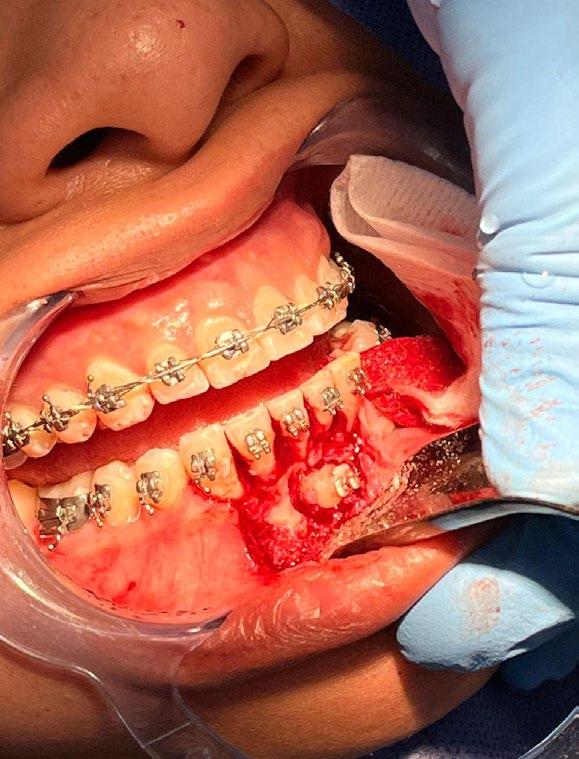

Paciente femenina de 30 años de edad que acude a consulta privada para segunda valoración ortodóntica debido a un mal tratamiento llevado a cabo en otro sector privado (Figura 1). Tras una correcta anamnesis y valoración, se realizó la propuesta de tratamiento de un trasplante dental, considerando que la paciente cumple con las características clínicas y biológicas requeridas para dicho procedimiento (Figura 2).

Previa asepsia y antisepsia, más colocación de campos en forma habitual, mediante infiltración troncular y de forma local, se realiza incisión

marginal con descarga lineal para levantar un colgajo seminewman (Figura 3). Se realiza ostectomía y osteotomía para liberar el órgano dentario retenido y facilitar su extracción (Figura 4). Una vez fuera de la cavidad bucal, se realiza tratamiento de conductos y obturación. De forma simultánea, se lleva a cabo la extracción atraumática del órgano dentario 73 (Figura 5) y la preparación alveolar del lecho receptor para recibir el órgano dentario a trasplantar bajo parámetros quirúrgicos (Figura 6).

Se enfatiza la mínima manipulación de los tercios radiculares del órgano dentario a trasplantar, intentando preservar, en lo posible, las fibras del ligamento periodontal. Se mantienen condiciones de hidratación a base de agua bidestilada durante su preparación, así como la sustitución neurovascular en su forma extrabucal. A nivel de los lechos receptores, se sigue un protocolo bacteriostático y bactericida no quelante.

En la zona postextracción del canino retenido (Figura 7), se realiza la conformación con materiales biocompatibles a base de xenoinjerto bovino y membrana de colágeno, para favorecer la correcta reparación de los tejidos blandos y duros, dadas las dimensiones del probable defecto, finalizando con sutura absorbible Vicryl 3-0 (Figuras 8 y 9).